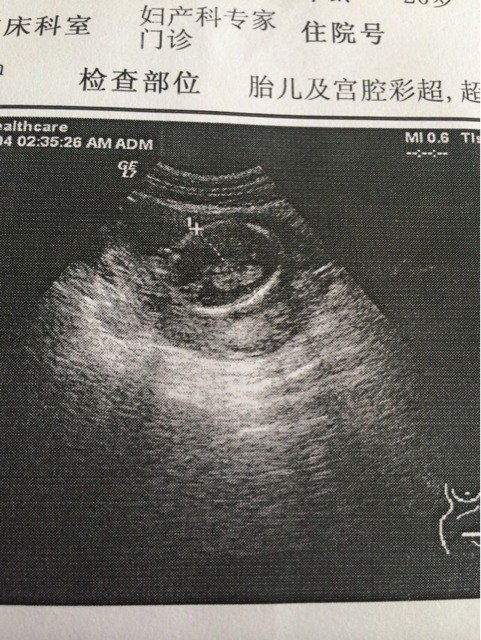

哪位大神会看是男是女?我想要女孩 哪位大神会看是男是女?我想要女孩😁😁 点击展开 郭筱雪99 2014-11-05 20:29 为您推荐: 其他回答 女孩,,, 139*****079_2abL 2014-12-10 08:33 我会看肚子 139*****079_2abL 2014-11-05 20:54 我听别人说,看那个心跳加速就是女儿 原味的薇笑 2014-11-05 20:53 这样怎么看的清楚 原味的薇笑 2014-11-05 20:50 ^_^ ^_^ 乄情如毒物、吸进则窒息 2014-11-05 20:40 加载更多 相关问题 这个小孩我想要,请问各方面正常吗?谢谢了,大神帮忙啊 我想要小孩 排卵期吃消炎药还有可能怀孕吗大神们帮帮忙 我想要一个宝宝,不知道怎样才能输出一个健康的宝宝求大神帮助